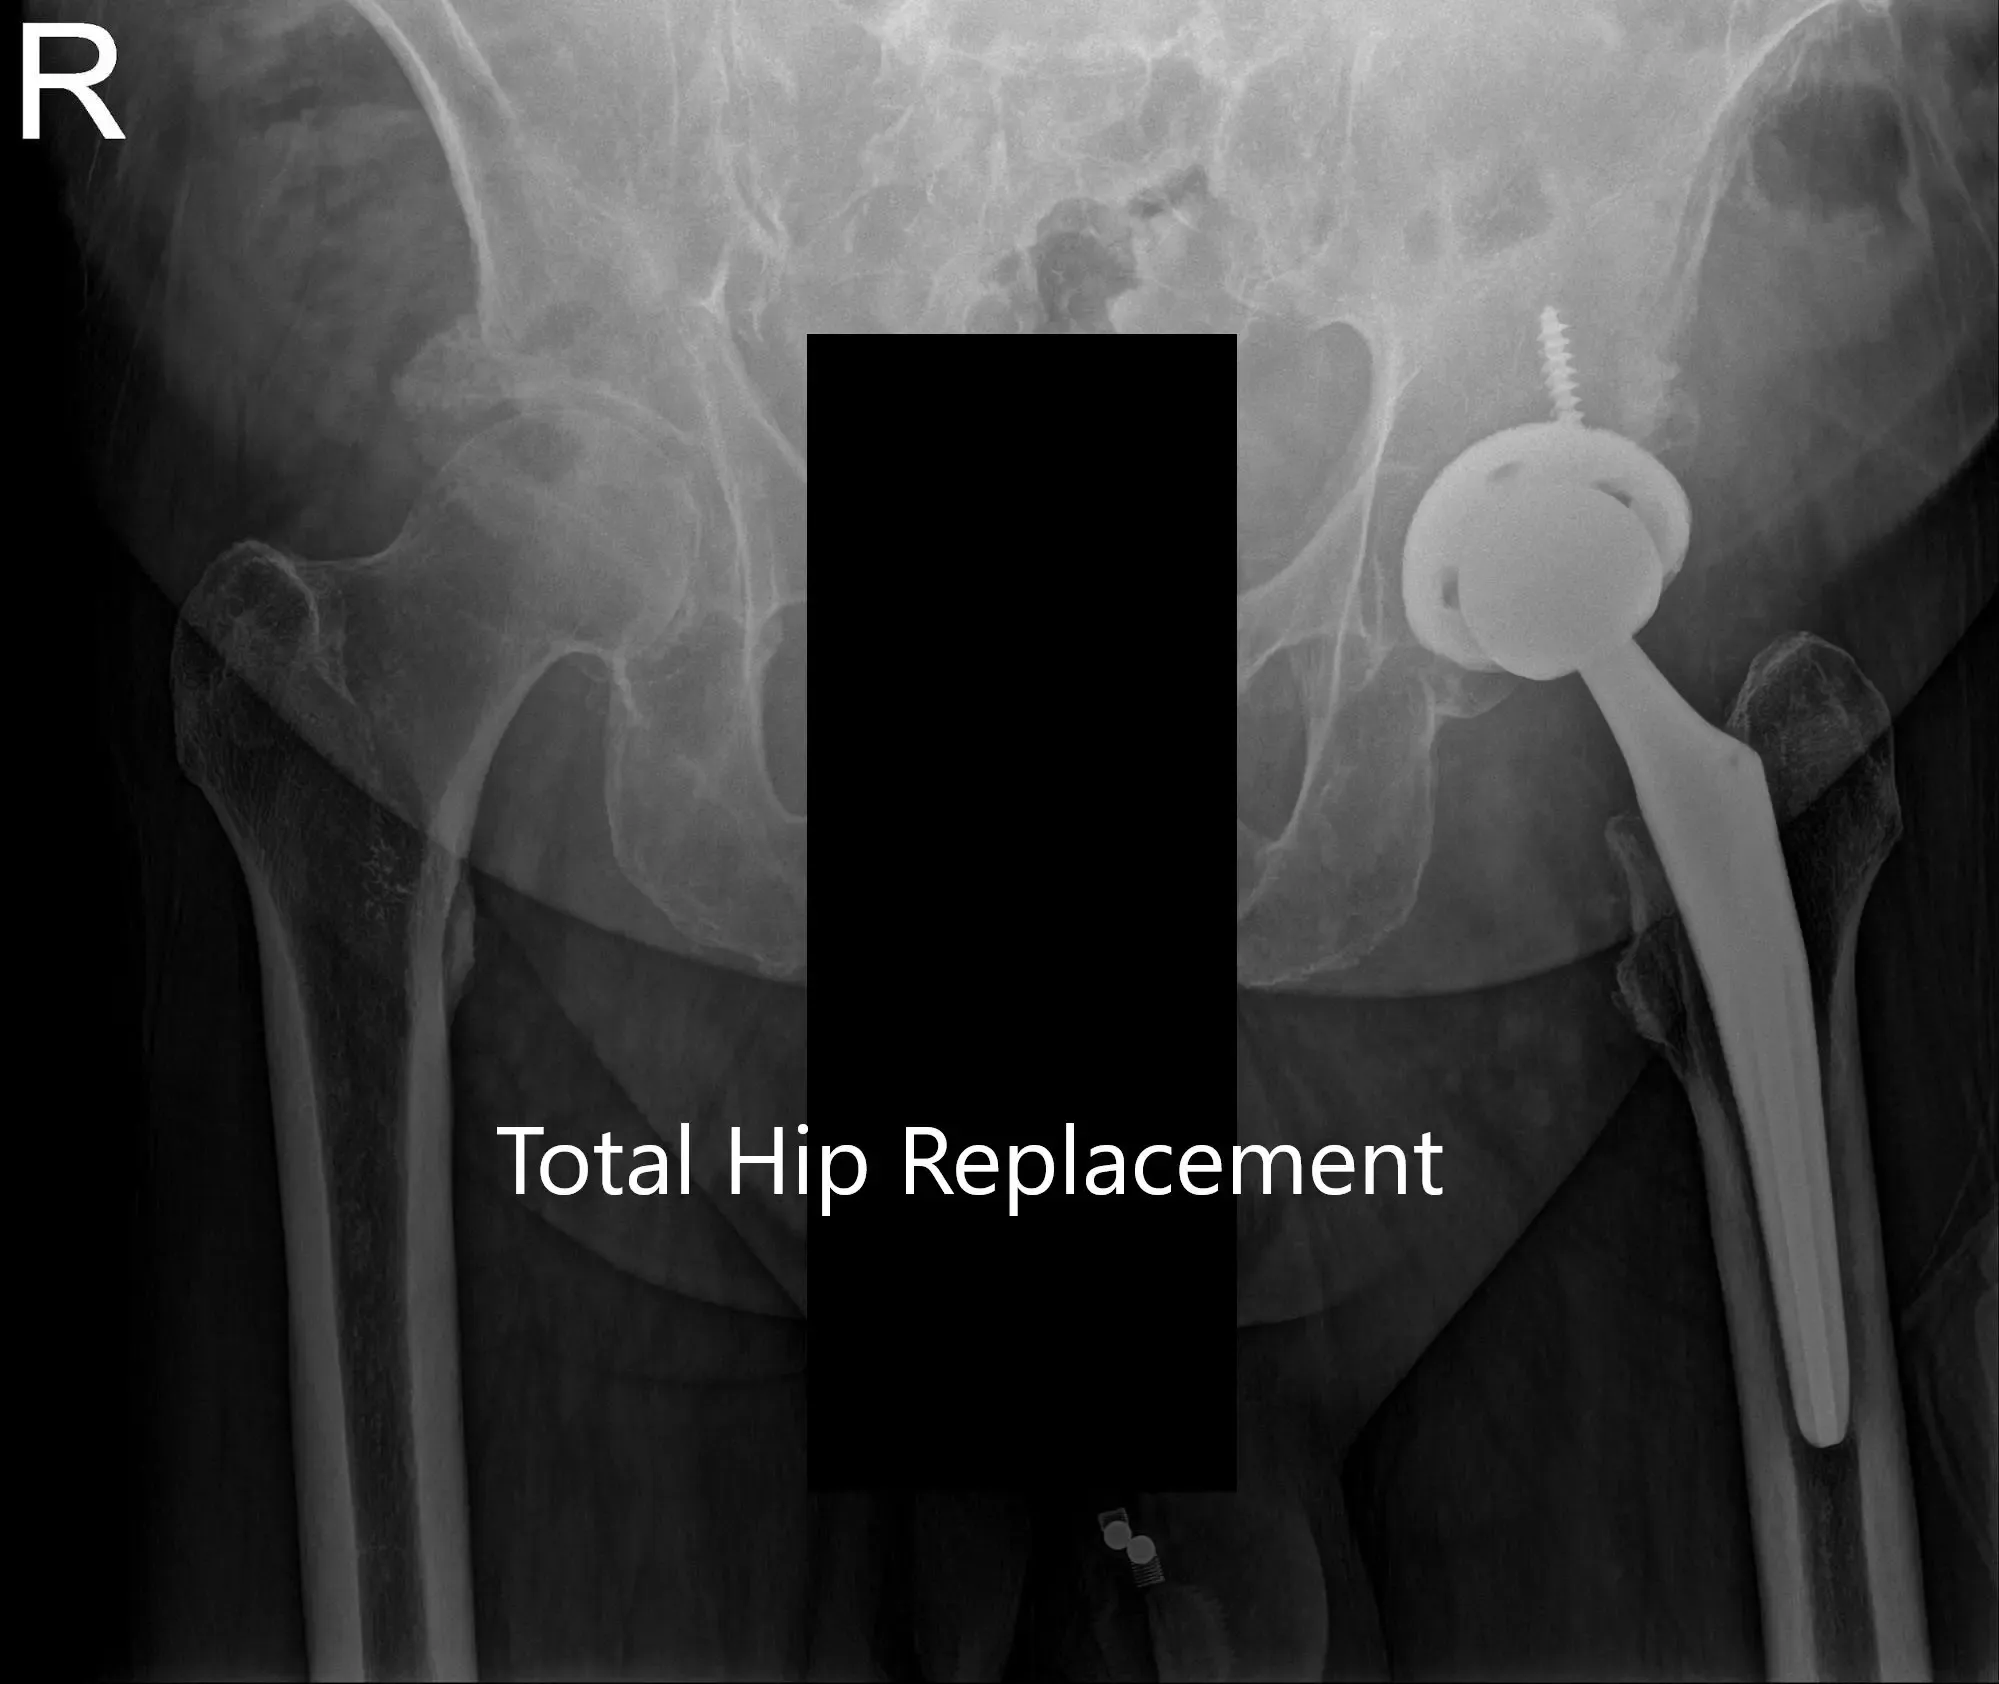

IMPLANTE UTILIZADO: Carcasa de acetábulo de 54 mm con inserto de polietileno de 0 grados, diámetro interior de 36 mm con cabeza femoral, 36 mm más 5 con tornillo de 6,5 mm x 30 mm.

Radiografía postoperatoria de la pelvis y vista lateral de la cadera izquierda.